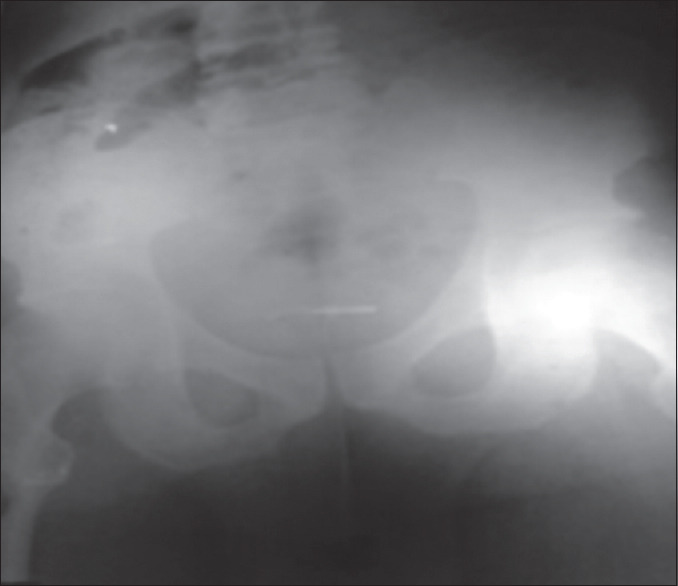

Apart from iatrogenic causes, many of the foreign bodies in the bladder and urethra are self-inserted through the urethra as a result of psychiatric disturbances, sexual gratification, or erotic curiosity while intoxicated. Despite the reports on the presentation of urethrovesical foreign bodies in the medical literature, the insertion of foreign bodies through the urethra for the purpose of erotic satisfaction remains an enigma. Here, we report a case of a knotted earphone jack as an urethrovesical foreign body inserted for erotic reason by a 32-year-old man with no history of psychiatric disturbances. He could not retrieve it, and the bladder foreign body remained in this position for about 8 h. He was referred to the accident and emergency unit of our hospital, and open surgery was performed to retrieve it.